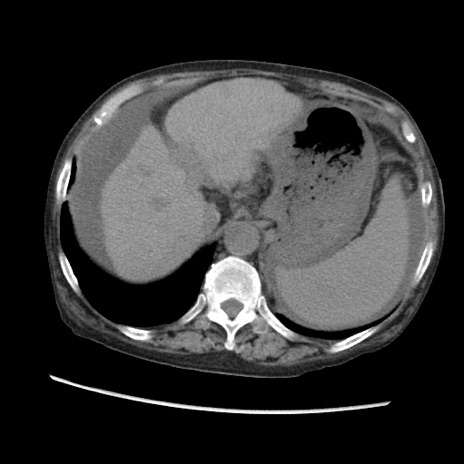

症例31(横断像)

【症例】80歳代 女性

【主訴】腹部膨満感

【現病歴】他院にて肝硬変にてフォロー中。1週間前から便秘、腹部膨満感、臍部腫瘤あり受診となる。

【既往歴】肝硬変

【身体所見】腹部膨隆あり、皮膚変化なし、疼痛なし。

【データ】WBC 4600、CRP 0.25